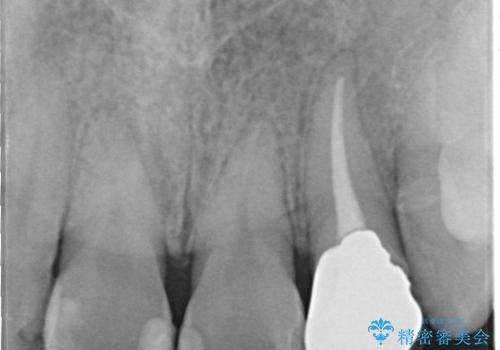

- 患者様は前歯にできものができたということで来院されました。

歯髄診断を行い、失活していると判断して根管治療を行いました。